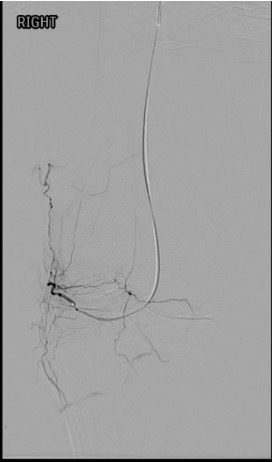

Selective catheterization: 4 Fr catheter (Cobra, Berenstein, or SOS Omni) to engage the popliteal; 2.0–2.4 Fr microcatheter coaxially advanced into each target genicular artery.

Angiographic hyperemia / synovial blush in the symptomatic territory is the primary target. This appears as a late-phase parenchymal blush beyond the normal capsular stain.

Reassess after each vessel — completion angiogram to confirm treatment of the blush and exclude non-target deposition.

Pre-embolization selective genicular angiogram demonstrating hypertrophied vessels and synovial hypervascularity in the territory of the patient's pain.Post-embolization angiogram showing pruning of the abnormal hypervascularity with preserved flow to normal tissue — the desired endpoint.